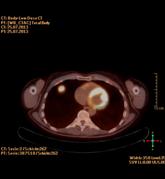

Die PET/CT ist in der Medizin derzeit die modernste zur Verfügung stehende bildgebende Untersuchung in der Diagnostik von Tumorleiden. Sie ermöglicht oft, sehr kleine Herde früher als mit anderen Verfahren wie Kernspintomographie (MRT) oder alleiniger Computertomographie (CT) zu entdecken. Ein besonderer Vorteil des Verfahrens besteht in der Kombination zweier bildgebender Verfahren, die sich perfekt ergänzen. Durch die CT Technik können Körperregionen und mittlerweile auch der gesamte Körper als vollständiger, lückenloser Datensatz erfasst werden. Dadurch entstehen Bilder in bis dahin ungeahnter Schnelligkeit und Qualität. Im PET werden im Gegensatz zum CT in erster Linie funktionelle Stoffwechselvorgänge im Körper dargestellt. Dazu wird Ihnen radioaktiv markierter Zucker (Glucose) in minimaler Menge in eine Vene injiziert. Die Verteilung im Körper wird mit einer speziellen Kamera (PET/CT-Scanner) gemessen, die Schnittbilder des Körpers gewinnt.

Die Glucose wird mit dem Radionuklid Fluor-18 markiert, das eine Halbwertzeit von 110 min hat. Das bedeutet, dass alle 2 Stunden die Radioaktivität um die Hälfte abnimmt. Zusätzlich wird innerhalb der ersten 2 Stunden ein Großteil der Radioaktivität über den Urin ausgeschieden. Insgesamt ergibt sich daraus eine durchschnittliche Strahlenbelastung von 6 mSv. Durch die PET wird also das Doppelte der natürlichen jährlichen Strahlenbelastung verursacht.

Zusammen mit der PET wird in der gleichen Untersuchung eine Computertomographie (CT) durchgeführt. Je nach Fragestellung und wenn schon Voraufnahmen vorhanden sind, wird das CT meist als Niedrig-Dosis CT ohne Röntgenkontrastmittel gefahren, d.h. mit niedriger Strahlenbelastung aber eingeschränkter Erkennbarkeit von anatomischen Details.

Ein Hybridgerät zwischen PET und CT in 64-Zeilen Technik wie am Klinikum Ludwigshafen kombiniert also in idealer Weise die detailgerechte hoch ortsaufgelöste Abbildung morphologischer und funktioneller Krankheitsaspekte insbesondere im Bereich der Onkologie.